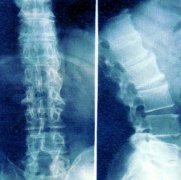

X线可以检查出脊柱关节变化也是诊断强直性脊柱炎的主要依据,脊柱的X线改变大多发生在骶髂关节改变之后,脊柱X线片早期可见骨质疏松, 强直性脊柱炎中晚期 出现方椎,脊椎间骨桥形成竹节一样的病变。 脊椎局部有小范围骨质硬化和破坏,这是早期X线的迹象,硬...[详细] 2024-12-28